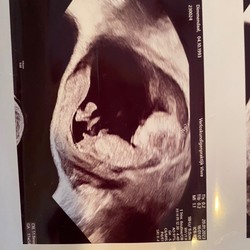

Wat denken jullie ?? 13 weken

Meisje!

🩷